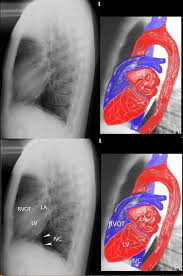

Lateral Chest X Ray Cardiomegaly Heart

The term cardiomegaly refers to an enlarged heart seen on any imaging test including a chest x ray. A 35 year old woman with a history of arrhythmia and liver failure. Annotated x ray of this same patient. But for the purpose of realism and the proper detection of the problem the doctors advise patients to have a cardiomegaly x ray done.

Hover on off image to show hide findings.

If the heart is enlarged on an x ray other tests will usually be needed to find the cause. Tap on off image to show hide findings. The ctr measures the width of the cardiac silhouette and the thoracic. X ray images help see the condition of the lungs and heart.